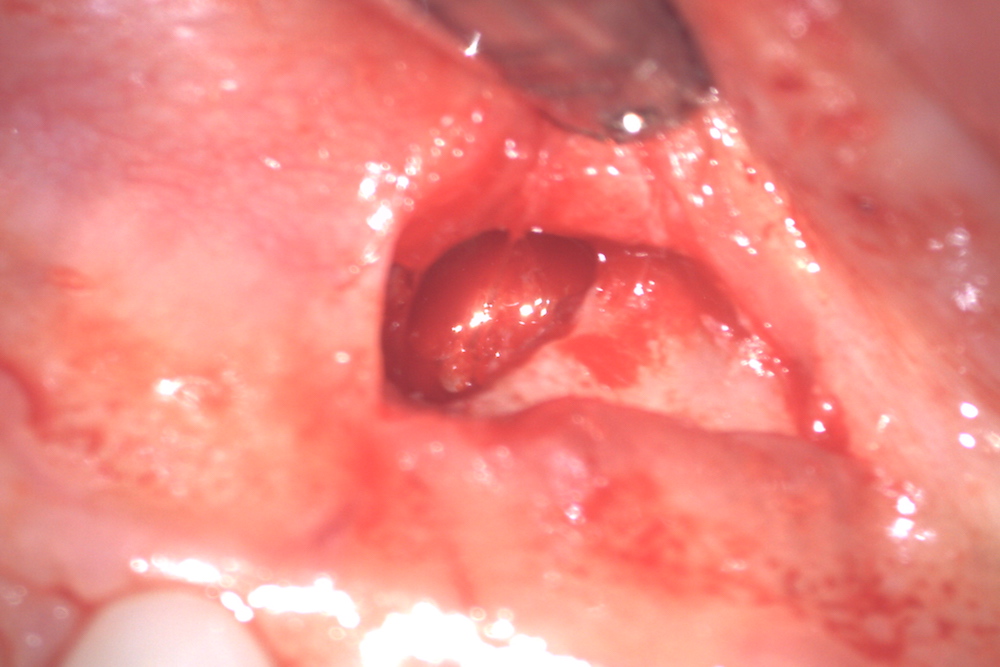

根管治療がうまくいかなかった場合などに、根っこの先っぽの方に「膿の袋」ができるケースがあります。

膿の袋があまりに大きいときには抜歯が必要になりますが、歯根端切除術は外科的に根尖という根の先っぽを切断して、膿の袋を同時に摘出する処置です。